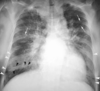

A

Consolidación alveolar

How well did you know this?

1